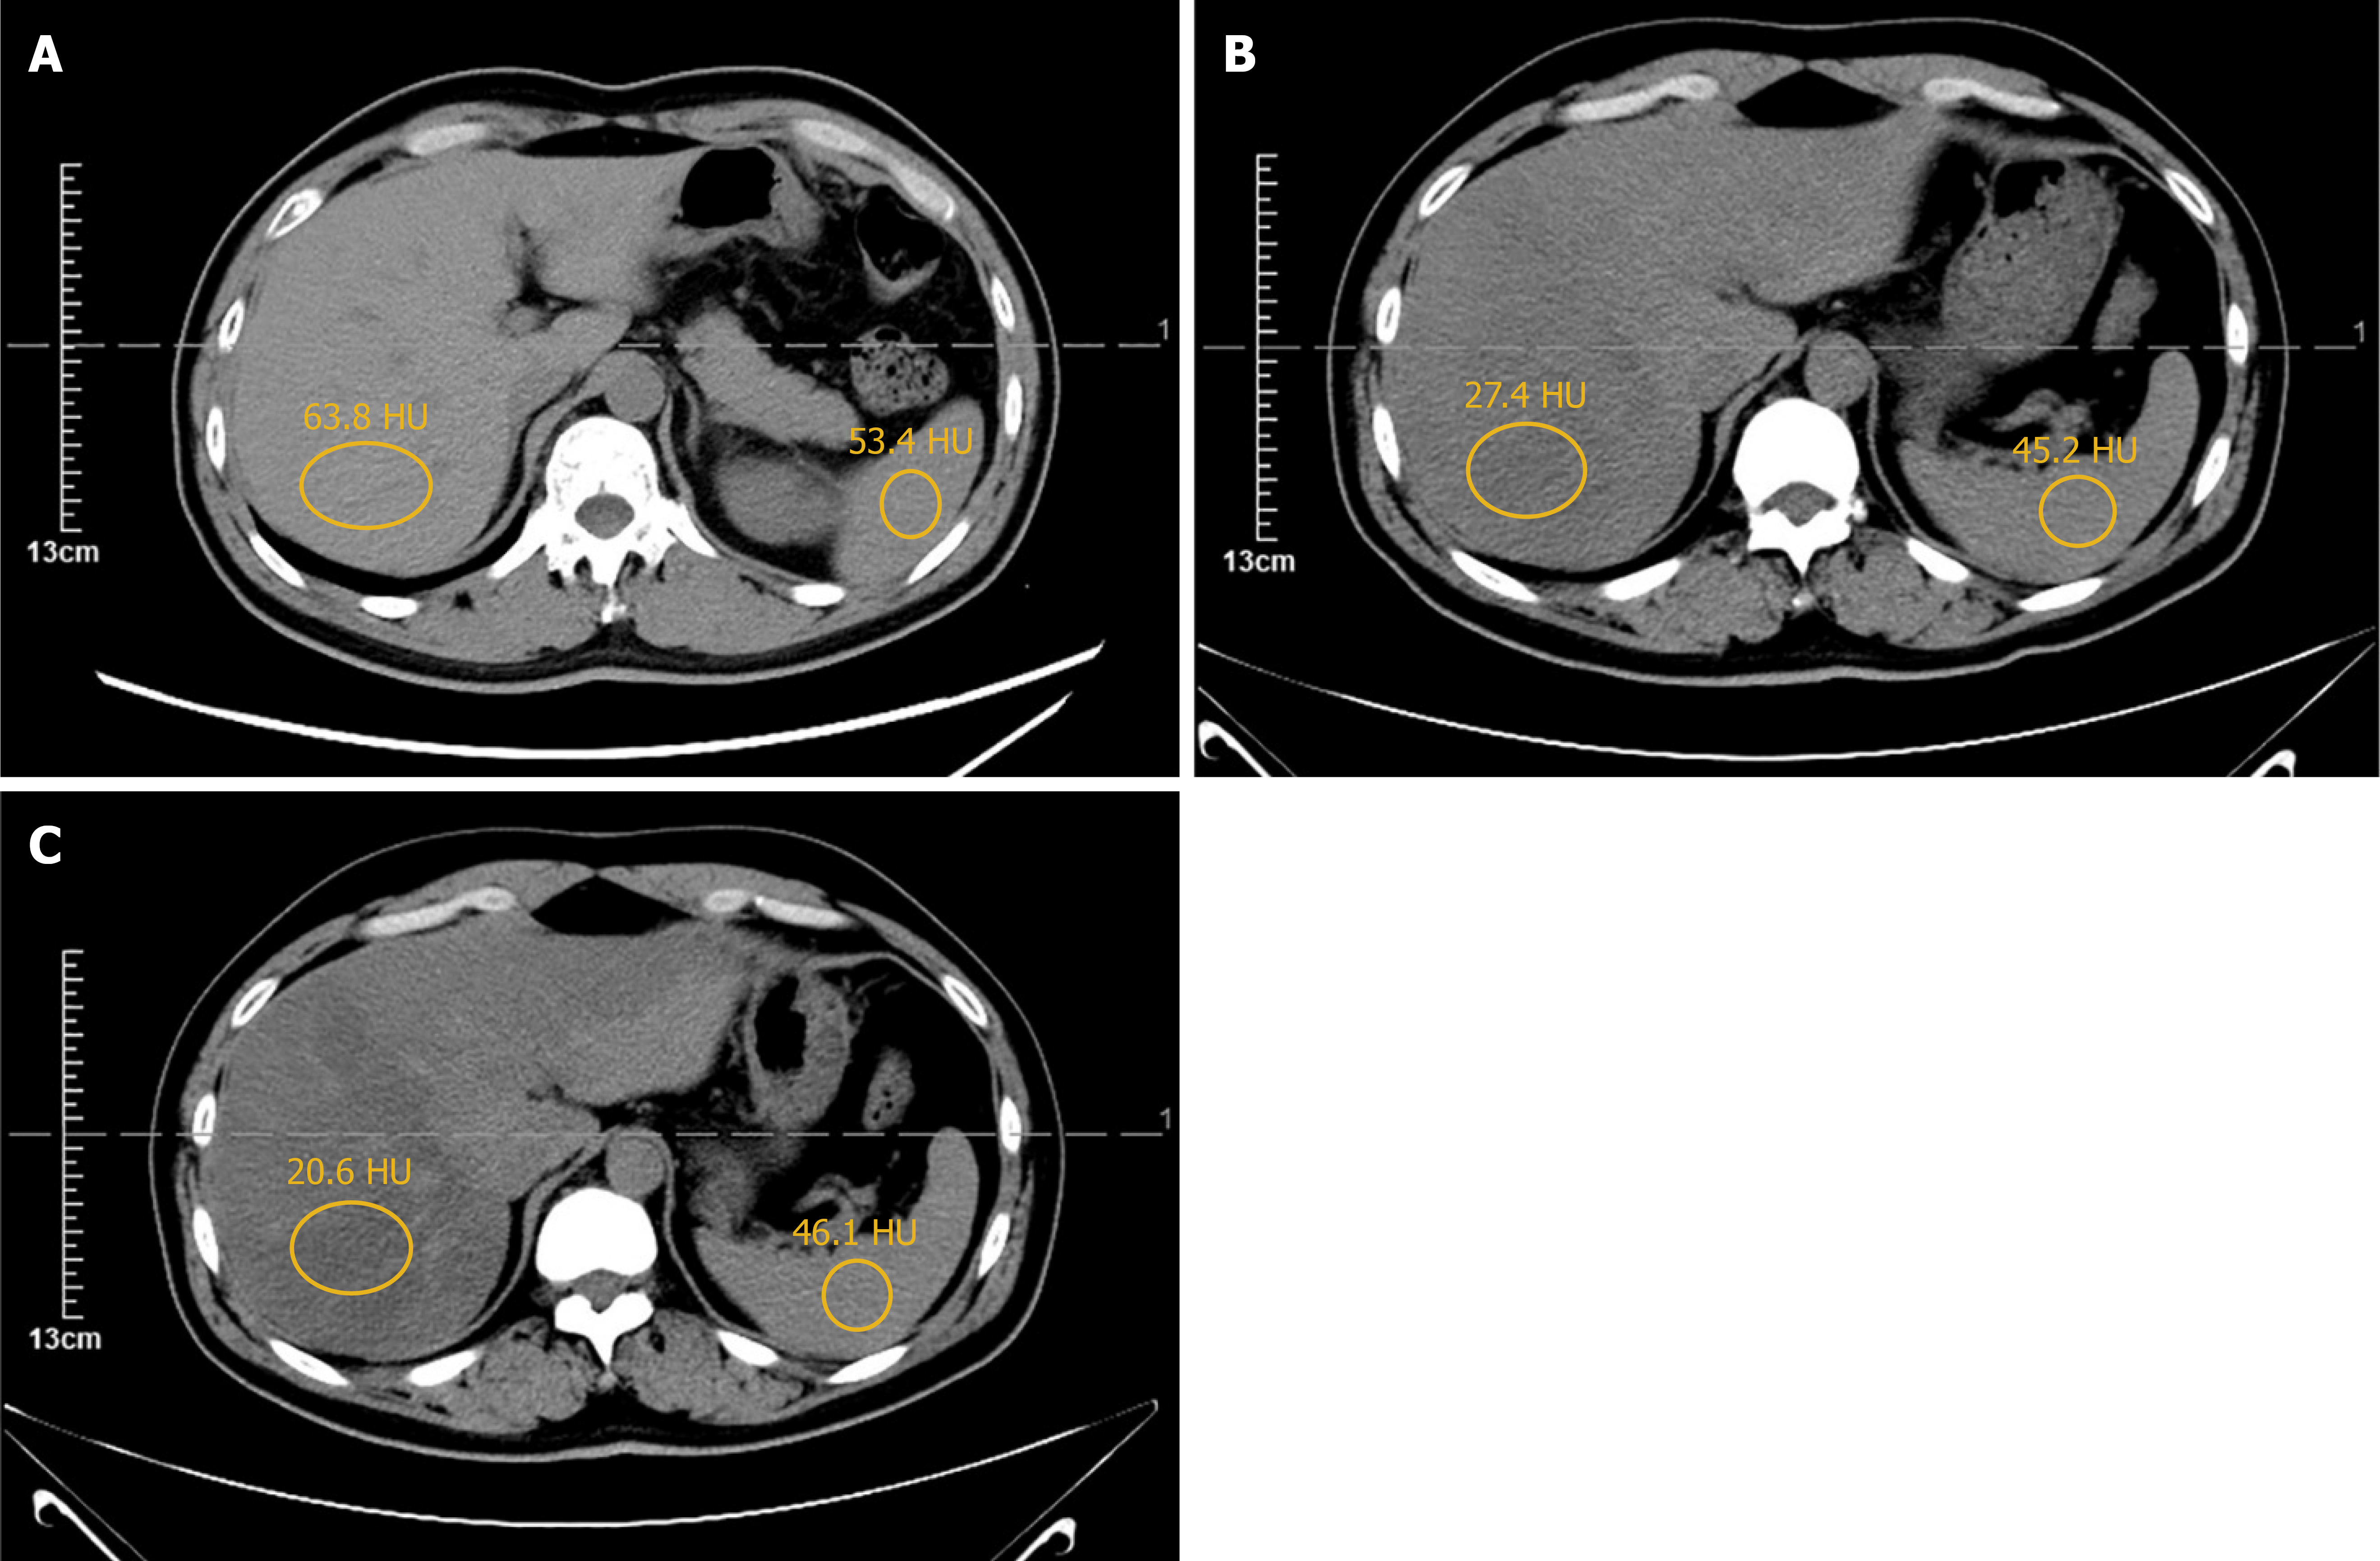

Colonoscopy revealed a 3.5-cm ulcerated, circumferential mass with irregular borders, located approximately 7 cm from the anal verge, consistent with features of malignancy. Histopathological analysis of biopsy specimens confirmed a moderately differentiated adenocarcinoma. Preoperative contrast-enhanced CT of the chest and abdomen demonstrated localized thickening of the rectal wall, without evidence of distant metastasis, including the liver and lungs. Pelvic magnetic resonance imaging identified a mid-rectal lesion with a negative circumferential resection margin (CRM) and no pelvic lateral lymphadenopathy (Figure 1). Baseline unenhanced abdominal CT showed no evidence of hepatic steatosis: Mean hepatic attenuation was 63.8 HU and the liver-to-spleen attenuation difference was 10.4 HU; both well within the normal range. Follow-up unenhanced CT at 6 months and 9 months after surgery revealed newly developed diffuse hepatic steatosis, with mean hepatic attenuation dropping to 27.4 HU and 20.6 HU, respectively, while splenic attenuation remained stable at 45.2 HU and 46.1 HU. After ileostomy reversal, serial CT scans at 3, 6, 9, and 18 months revealed progressive resolution of fatty liver, with complete normalization by 3 months and no recurrence thereafter (Figure 2). Postoperative pathology confirmed moderately differentiated adenocarcinoma with no lymph node metastasis (0/12), and the pathological stage was pT3N0M0. Both the CRM and stapler resection margins were negative.

Figure 1

Figure 1 Preoperative abdominal computed tomography and magnetic resonance imaging. A: The transverse image shows a rectal lesion (indicated by the orange arrow) in the middle segment of the rectum with no obvious lymph node metastasis; B: The sagittal image clearly demonstrates the lesion in the middle rectal segment (orange arrow) and further confirms the absence of significant lymph node metastasis; C: The plain abdominal computed tomography scan indicates no significant liver metastasis (the circle mean hepatic attenuation: 63.8 HU; splenic attenuation: 53.4 HU); D: The contrast-enhanced abdominal computed tomography scan further confirms the absence of significant metastatic lesions in the liver.